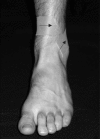

Figures